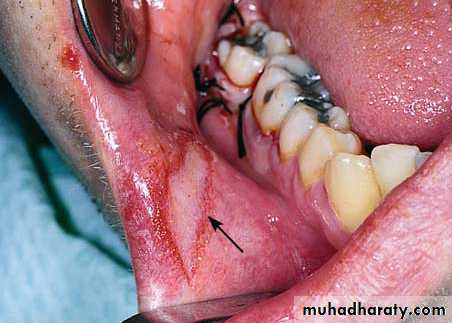

• -Bleeding at wound margins

• -Bleeding at a bony foramen within the socket

VII. Postoperative Bleeding

• Cause